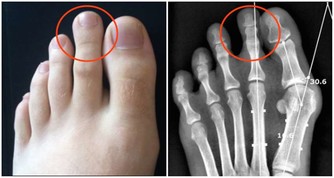

刺梨聽過這名字的人想必都很少,其實它屬於薔薇科植物繅絲花的果實,又名茨梨,被稱為天然維C之王,富含的多種微量元素,可促進體內新陳代謝,排出卵巢中的毒素廢物。

女人如果補充了足夠的維生素,患卵巢癌的機率能降低到一半,每天用3-5顆刺梨幹泡水喝,輕鬆讓卵巢恢復年輕活力。